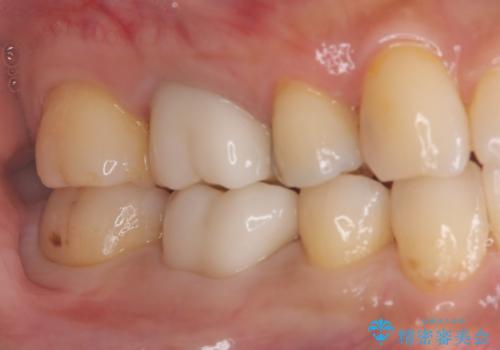

ズキズキ痛い歯 オールセラミッククラウンによる修復

- 冷たいもので長引く痛みがあることを主訴に来院されました。

抜髄を行い、オールセラミッククラウンにて修復を行いました。

- 26万円費用は治療当時の料金となります

根管充填はバイオセラミックシーラーを使用しています。